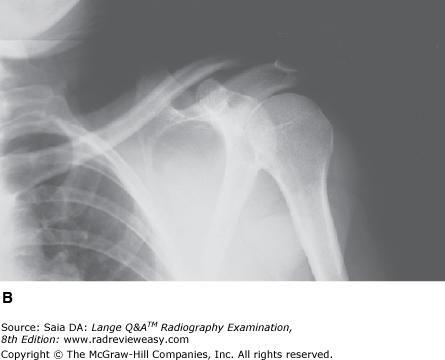

Which of the following statements is (are) true regarding the radiograph in Figure 2–12?

D 1, 2, and 3

-A right scapular Y is illustrated; this refers to the characteristic Y formed by the clearly visible humerus, acromion, and coracoid. The patient is positioned in a PA oblique position—in this case, an RAO projection to demonstrate the right side. The MCP is adjusted to approximately 60 degrees to the IR, and the affected arm is left relaxed at the patient's side. The scapular Y position is employed to demonstrate anterior or posterior humeral dislocation. The humerus is superimposed on the scapula in this position; any deviation from this may indicate dislocation.